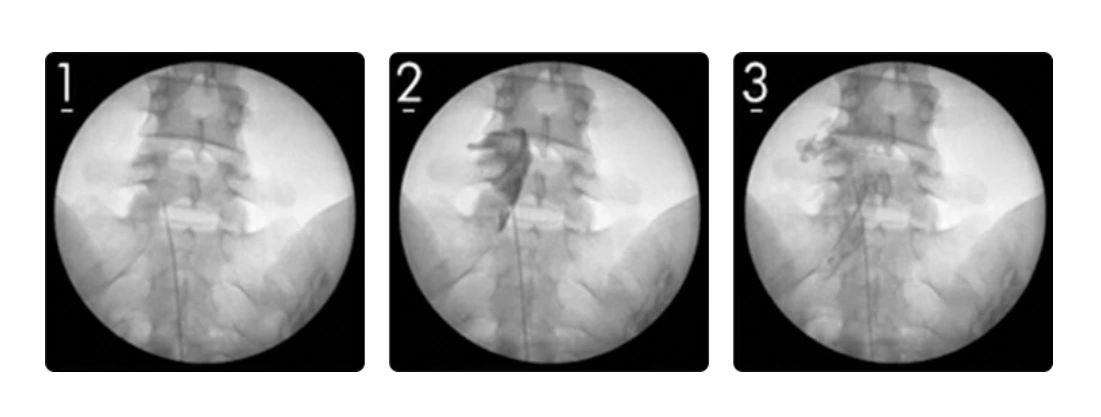

실시간 영상(C-ARM)으로 보면서 통증을 일으키는 신경뿌리를 찾아 주사로 약물을 투여하여 신경부종이나 염증을 가라앉혀 통증을 줄여주는 치료입니다. 시술 시간이 짧지만 직접적으로 통증 부위에 약물을 주사하기 때문에 통증을 없애는데 효과가 좋고 목과 허리 등 다양한 부위에 사용되지요.